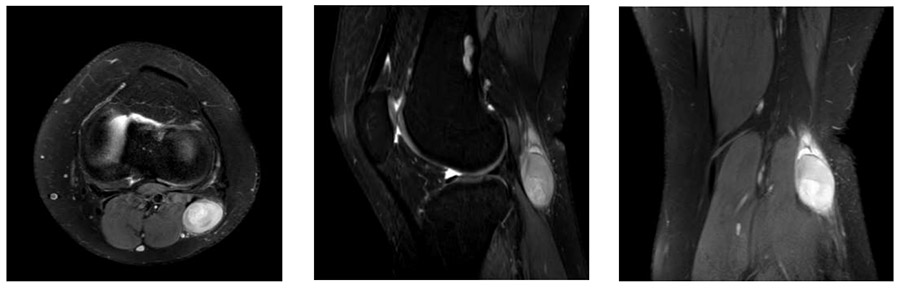

İlk Başvuru: İlk ameliyat öncesi MR’da diz posterolateralde düzensiz sınırlı heterojen yumuşak doku kitlesi görülmekte

Ameliyat Öncesi: İlk ameliyat sonrası kontrol MR’da kalıntı tümör dokusu ve çevreleyen ödem görülmekte